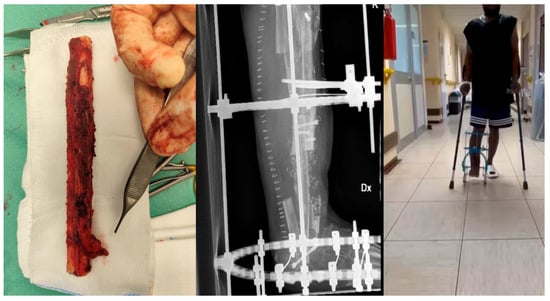

Within our cohort, several highly complex cases were managed through coordinated collaboration between orthopedic surgeons, infectious disease specialists, plastic surgeons, and interventional radiologists (Figure 2). Our findings underscore the critical impact of chronicity on the treatment complexity, demonstrating that infections treated beyond 90 days from the initial trauma were associated with a notably higher surgical reintervention rate (67% vs. 37%). This observation aligns closely with established literature. Similarly, Niebuhr et al., in their systematic review, identified chronic infection as a major risk factor for subsequent treatment failure [24].

Figure 2.

39-year-old male with a history of distal tibial metaphyseal fracture treated with ORIF, complicated by chronic osteomyelitis. He underwent one single stage surgical procedure including fistulectomy, partial tibial resection with 3 × 5 cm cortical window, debridement, and antibiotic cement placement, covered with a peroneal perforator flap.